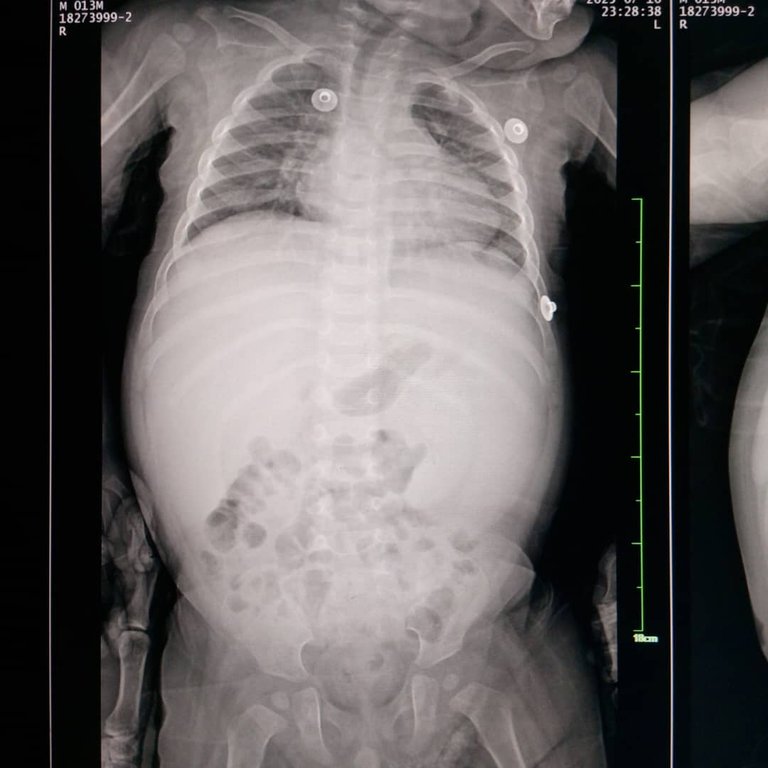

La enfermedad actual de Ander, el niño para quién solicité hace un par de días donantes de sangre, empieza cuando Ander tiene meses y 15 días. Comenzó con fiebre, diarrea e ictericia, (piel y ojos amarillos). Todo parecía un virus, lo llevaron al pediatra, quien le médico un antibiótico (cefotaxima), le ordenó realizar una hematología, que al obtener los resultados, reporta una hemoglobina de 7.7, pero las fiebres altas continuaron. Cuando se le comunica al doctor, es él quién les indica que vayan a Maturín y le realicen otra hematología y un RX de tórax. Para ese momento, la hemoglobina de Ander ya había descendido a 5.5. Fue ahí, cuando asistieron al hospital donde actualmente está recluido. Es allí donde comienza todo el proceso.

Ander llegó a manejar una hemoglobina de 3.1 en esos días, ya que estaba haciendo hemólisis (destruyendo los glóbulos rojos) y una esplenomegalia en grado VIII (el Bazo) inflamado. Esta primera hospitalización de Ander, dura 19 días, lo estabilizaron y de ahí , partieron a Caracas con una hematólogo privada, la cual le mandó a realizar una serie de estudios especiales para tratar de llegar al diagnóstico. Allí duraron 9 días en Caracas-Venezuela.

Ander's current illness, the child for whom I requested blood donors a couple of days ago, began when Ander was 15 months old. It started with fever, diarrhea, and jaundice (yellow skin and eyes). It all looked like a virus, so they took him to the pediatrician, who prescribed an antibiotic (cefotaxime) and ordered a blood test. The results showed a hemoglobin level of 7.7, but the high fevers continued. When the doctor was informed, he instructed them to go to Maturín for another blood test and a chest X-ray. By that time, Ander's hemoglobin had already dropped to 5.5. It was then that they went to the hospital where he is currently being treated. That is where the whole process began.

Ander's hemoglobin level dropped to 3.1 during those days, as he was experiencing hemolysis (destruction of red blood cells) and grade VIII splenomegaly (enlarged spleen). Ander's first hospitalization lasted 19 days. They stabilized him and then left for Caracas with a private hematologist, who ordered a series of special tests to try to reach a diagnosis. They spent nine days in Caracas, Venezuela.